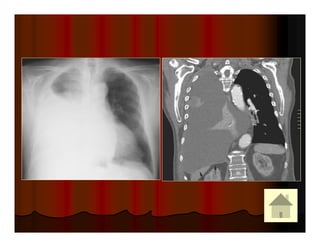

Cavitating squamous cell carcinoma: hang lệch tâm, thành hang dày

Female: cavitary lesions, metastatic squamous cell carcinoma (cervix).

Mỗi hang thường có một banh nấm